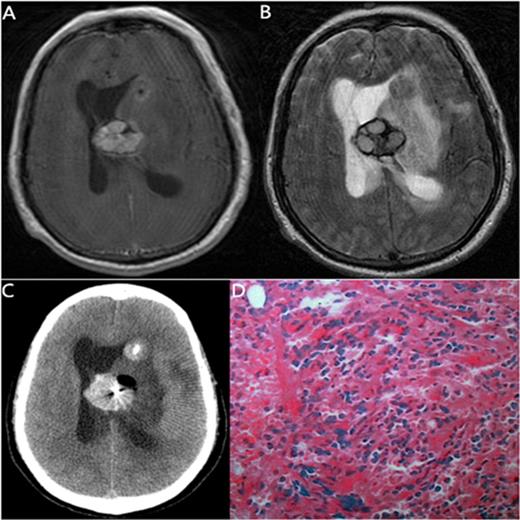

| 1 | 15/M | AML (M5) | 14/3 d after Cyclosporin | Seizure | MRI: The left occipital lobe, right frontal lobe low-density lesions with enhancement of capsule wall. | Infection | Fungal brain abscesses | Improved | |

The MRI, biopsy material and pathology of a 15-year-old man with AML (M5)